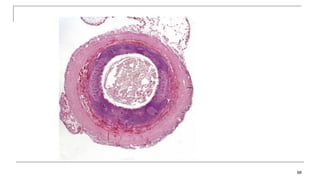

Larger Lymphatic Vessels, Trunks, and

 The lymphatic capillaries empty into larger lymphatic vessels, which are

similar to veins in terms of their three-tunic structure and the presence of

valves.

 These one-way valves are located fairly close to one another, and each

one causes a bulge in the lymphatic vessel, giving the vessels a beaded

appearance .